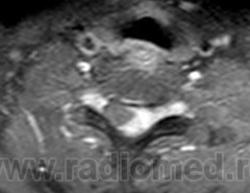

ГМ. СМ. Нейросаркоидоз. Саркоидоз на спинальном уровне. +

Саркоидоз на спинальном уровне.

journal_logo.jpgf24.largespinnogo_mozga_v_23-letniy_muzhchina.jpgf25.mediumspinnogo_mozga_v_23-letniy_muzhchina.giff26.mediumspinnogo_mozga_v_23-letniy_muzhchina.gif